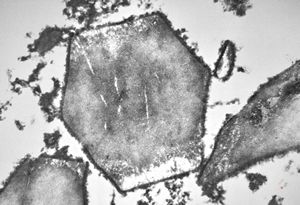

F,1y. | eosinophilic granuloma - Charcot- Leyden crystals

M,15y. | eosinophilic granuloma - Charcot- Leyden crystals

M,15y. | eosinophilic granuloma - Charcot-Leyden crystal

F,1y. | eosinophilic granuloma - Charcot- Leyden crystal